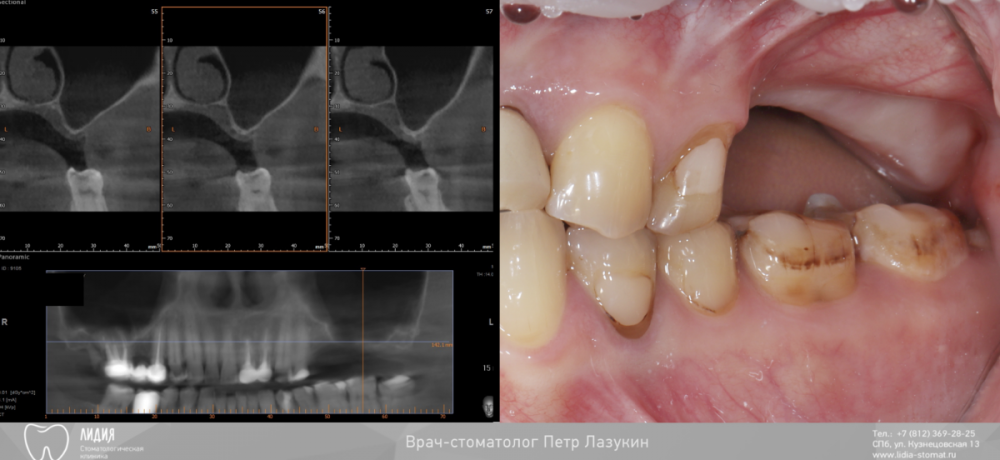

pit Опубликовано 22 декабря, 2021 Поделиться Опубликовано 22 декабря, 2021 Всем привет! Клинический случай. Реферативный пациент. В анамнезе несостоятельная костная пластика и несостоятельный синус-лифтинг (или даже два). Выбрана тактика: имплантация в позиции 25 27 28 (под углом 45 градусов) одномоментно с ОСЛ. В случае очередной неудачи протезирование было бы выполнено протезирование компромиссной конструкцией с опорой на 25 28 импланты. Во время операции произошел полный разрыв слизистой пазухи. Палатинальная стенка была скелетирована и к ней подшита мембрана с формированием купола. Уложен графт ИНТЕРОС, установлены импланты Хай-Тек. Швы. Протезирование МК коронками с винтовой фиксацией с уровня МЮ и платформ через 12 месяцев 13 1 2 Ссылка на комментарий

pit Опубликовано 24 декабря, 2021 Автор Поделиться Опубликовано 24 декабря, 2021 6 часов назад, plot сказал: Олично! Скажите Петр, чем обусловлен такой срок ожидания, 12 мес. обьемом аугментации? И достаточно ли мембраны на такое большое окно в синус? Планировалось 9 месяцев в связи с объемом резидуальной кости, но пациент пришел позже. да, достаточно. Латеральная стенка не участвует в стабилизации импланта Ссылка на комментарий